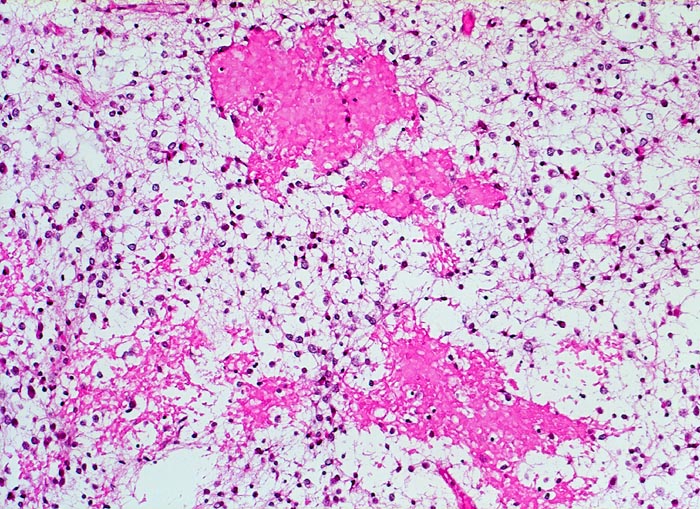

PathoPic – image database / PathoPic ID 5258 - Oligodendrogliom (WHO Grad II)

Oligodendrogliom (WHO Grad II)

Hirn frontal

Frische Einblutungen

Oligodendrogliome zeigen häufig Einblutungen

Histologie

100